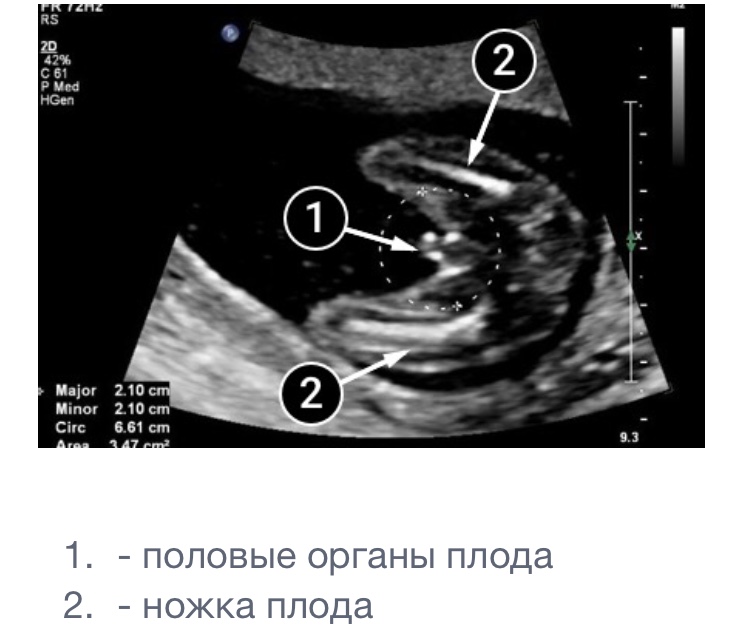

Нам позавчера сказали мальчик☺️☺️☺️ 16 недель, мне прям не верится по этому не закрашиваю). Но картина маслом прям была, очень жаль что фоточки не распечатала врач☹️, но я нашла в интернете картинку прям такую же). Только причинное место ещё лучше видно было😁, надеюсь ко второму скринингу ничего не рассосётся 🤦🏻‍♀️😄